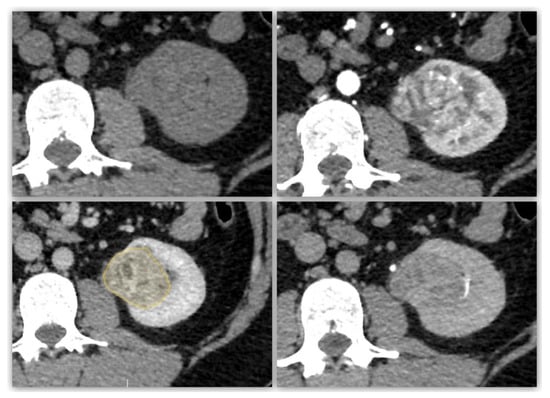

Figure 2. Representative case of segmentation for a clear cell renal cell carcinoma (ccRCC). A 55-year-old man with a demarcated, well-defined, homogenous tumor, with a regular calcification, diagnosed as a ccRCC, at multiphasic contrast-enhanced CT scan: unenhanced (upper left), arterial (upper right), nephrographic (lower left) and excretory (lower right) phases. Red outline represents tumor segmentation.

All Digital Imaging and Communication in Medicine images were anonymized. Segmentation was performed by C.G. using SOPHiA DDM for Radiomics v2.1.21 (SOPHiA GENETICS, Saint-Sulpice, Switzerland). In accordance with previous studies, nephrographic phase images were segmented due to their favorable tumor/renal parenchymal contrast. First, the slice on which the tumor was clearest (axial, coronal or sagittal plane) was chosen, and the tumor contours were precisely drawn by hand. Next, a volumetric model of the tumor was constructed using a deformation algorithm. If necessary, the user could manually adjust the semi-automatically obtained contours of the lesion. Each 3D segmentation process took approximately 20 min. The user interface of the segmentation software is shown in Figure 3.

Figure 3. Three-dimensional (3D) segmentation software interface for a clear cell RCC. Tumor segmentation on 2D slice at nephrographic phase (yellow outline, left), with corresponding 2D segmentations on coronal and sagittal plans (lower right), and a volumic model of the 3D segmentation (upper right) used for radiomic features extraction.